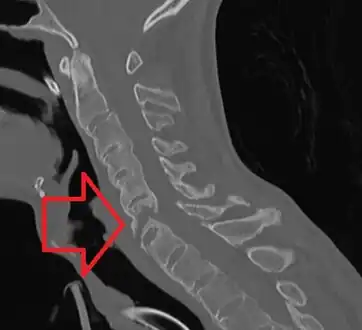

The earliest changes demonstrable by plain x–ray shows erosions and sclerosis in sacroiliac joints. Progression of the erosions leads to widening of the joint space and bony sclerosis. X-ray spine can reveal squaring of vertebrae with bony spur formation called syndesmophyte. This causes the bamboo spine appearance. A drawback of X-ray diagnosis is the signs and symptoms of AS have usually been established as long as 7–10 years prior to X-ray-evident changes occurring on a plain film X-ray, which means a delay of as long as 10 years before adequate therapies can be introduced.[21]

Options for earlier diagnosis are tomography and MRI of the sacroiliac joints, but the reliability of these tests is still unclear.

CT scan showing bamboo spine in ankylosing spondylitis -